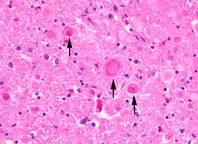

Die Wissenschaftlerinnen und Wissenschaftler untersuchten histologische Proben von vier erkrankten Hunden und entdeckten in der grauen Substanz der Gehirnhälften, dem Kleinhirn, dem Hirnstamm und in den sensorischen Bahnen des Rückenmarks auffällige Ansammlungen. Diese abweichenden Bereiche beinhalteten sogenannte Autophagosomen. Autophagosomen sind Zellbestandteile, die während der Autophagie – dem Abbau von zelleigenem Material – entstehen. Eine Ansammlung von Autophagosomen stört die normalen Abläufe des Nervensystems.